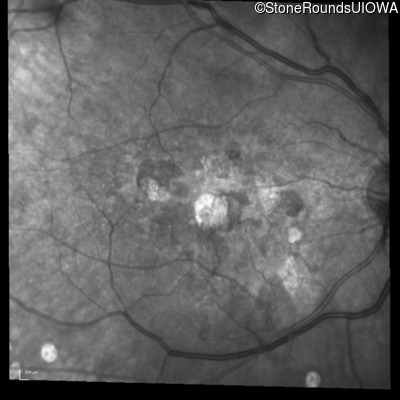

Visit at age: 60 years (Visit 2)

Infrared Fundus Photograph - Right - 20/100

Exemplar